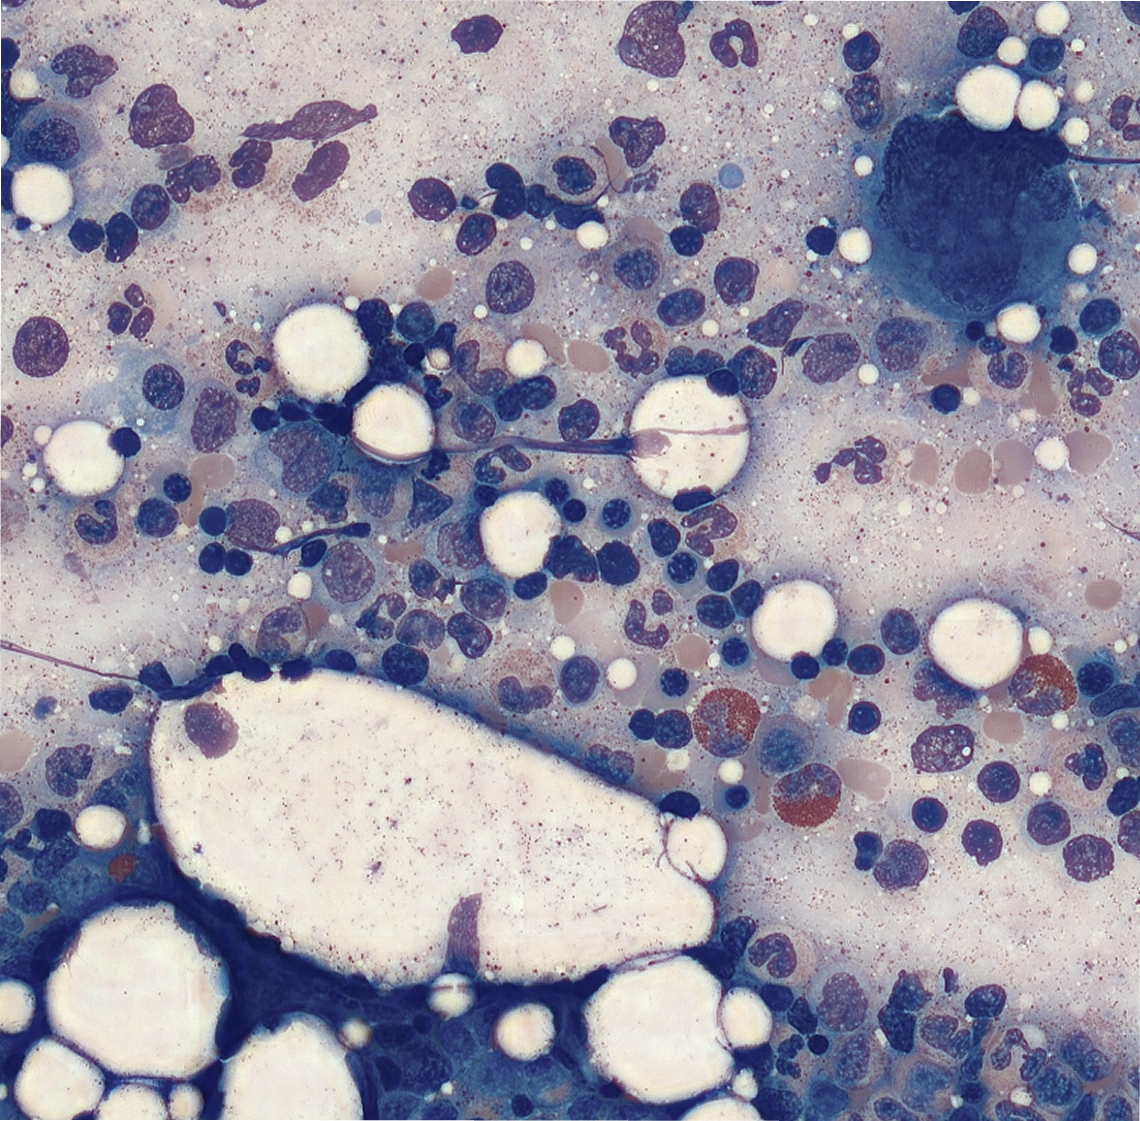

Detecte y analice automáticamente 200 glóbulos blancos, preclasificados en 16 categorías. Reclasifique, marque y anote células fácilmente sin perder el contexto completo.

Estimación de plaquetas y detección de agregados en 10 campos de visión, sin necesidad de conteo manual.

Analice múltiples láminas por caso, priorice anomalías y etiquete hallazgos para segundas opiniones, capacitación o investigación.

Evaluación integral de las reservas de hierro en muestras teñidas con azul de Prusia.

Explore muestras reales de sangre periférica y médula ósea. Haga zoom, aleje la imagen y explore el contexto completo. Experimente la diferencia Full-Field.